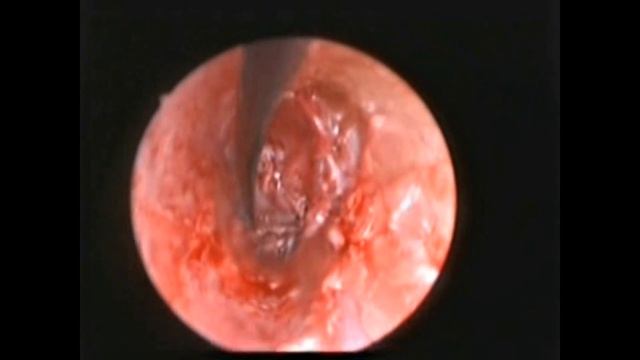

Rzayev R.M. - Перфорация барабанной перепонки - Эндомеатальная эндоскопическая мирингопластика смотреть онлайн

17:20

Rzayev R.M. - Перфорация барабанной перепонки - Эндомеатальная эндоскопическая мирингопластика

Уход и лечение: медицинские процедуры 982 просмотров